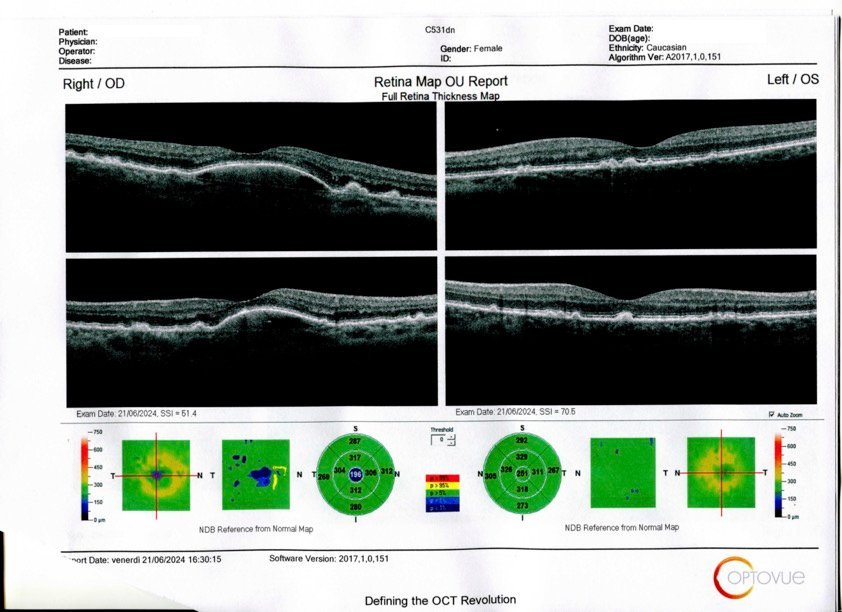

Al controllo, l’OCT ha evidenziato inequivocabilmente una riduzione del dep tanto da suscitare meraviglia anche nel medico. Ha detto che delle “fluttuazioni” sono possibili, però ha voluto sapere tutto sui trattamenti di agopuntura che la persona stava facendo.